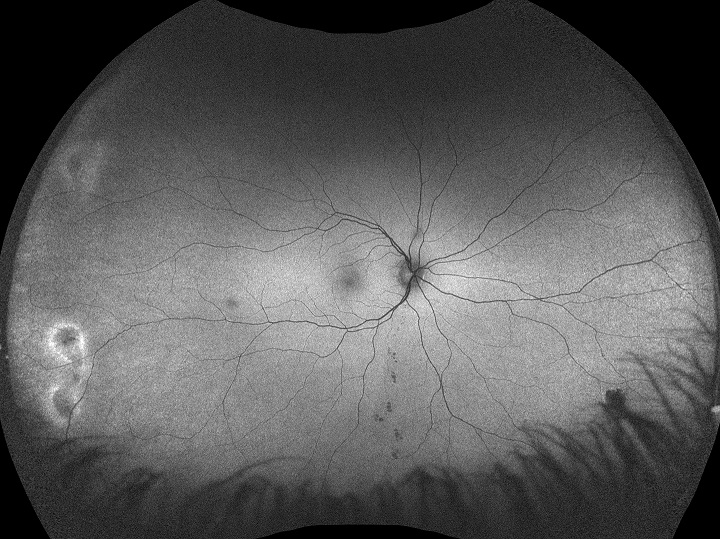

Silverstone est l’outil le plus performant du marché pour l’examen de la rétine. Le seul appareil d’imagerie de la rétine ultra-grand champ avec un OCT Swept-Source intégré, Silverstone produit une image optomap en une seule prise en moins d’½ seconde et permet un balayage par OCT guidé de l’ensemble de la rétine jusque dans la périphérie lointaine.

Silverstone offre les avantages suivants :

- L’ultra-grand champ avec OCT intégré Swept-Source facilite un examen détaillé de la rétine, du vitré à la sclère.

- L’OCT Swept-Source guidé ultra-grand champ permet de visualiser les pathologies en tout point de l’optomap.

- L’imagerie 3-in-1 color Depth™ permet d’obtenir d’importantes données cliniques, de la surface de la rétine à la choroïde.